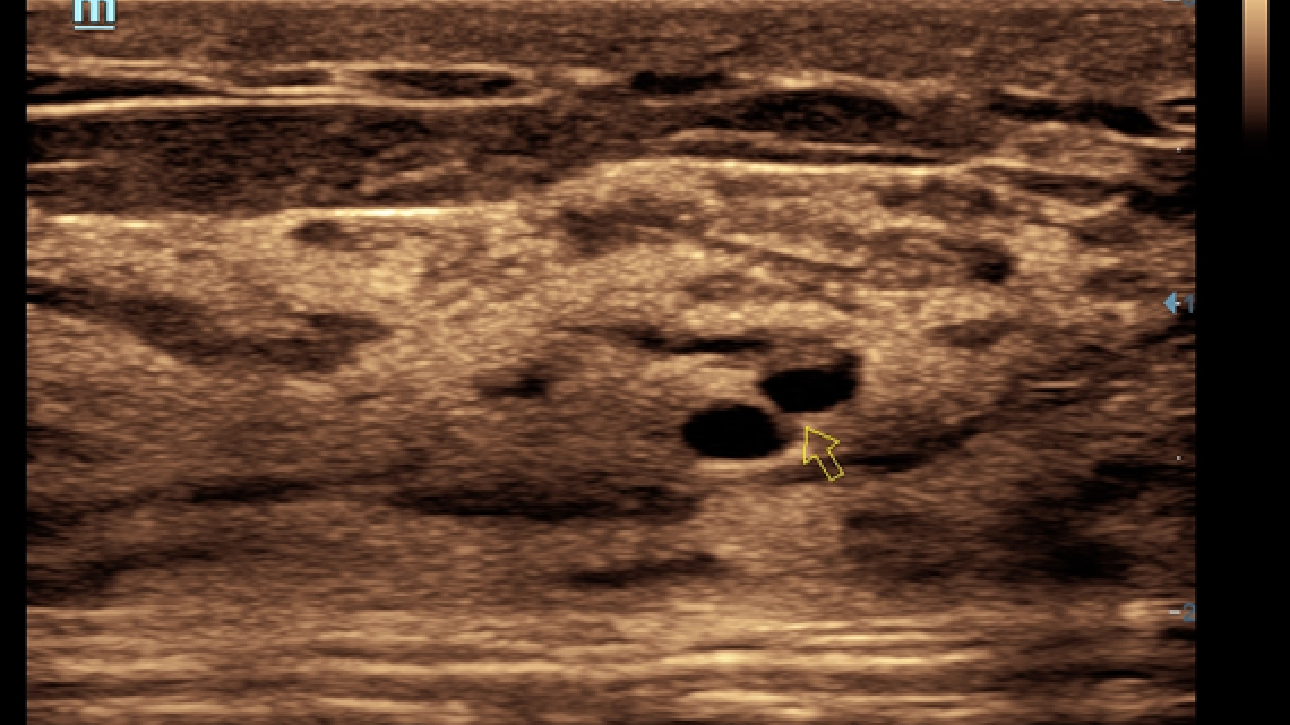

X-Insight ├© una soluzione completa studiata per offrire la migliore qualit├Ā diagnostica.

La nuova soluzione di Mindray ├© la traduzione pratica delle esigenze quotidiane dei clienti in soluzioni cliniche, il tutto con tecnologie ad ultrasuoni all'avanguardia ed in continua evoluzione.

Proponendosi come partner affidabile, DC-60 Exp con X-Insight si concentra su ci├▓ che conta veramente, semplificando la gestione della pratica clinica quotidiana con facilit├Ā e sicurezza.

Progettato per rispondere al meglio alle esigenze del cliente, DC-60 Exp con X-Insight ├© studiato per offrire un'efficienza elevata nel campo dell'imaging di precisione, grazie a una chiarezza immediata (eXpress Clarity), allŌĆÖeccezionale intelligenza (eXceptional Intelligence), oltre a vantare una lunghissima esperienza (eXceeding Experience).